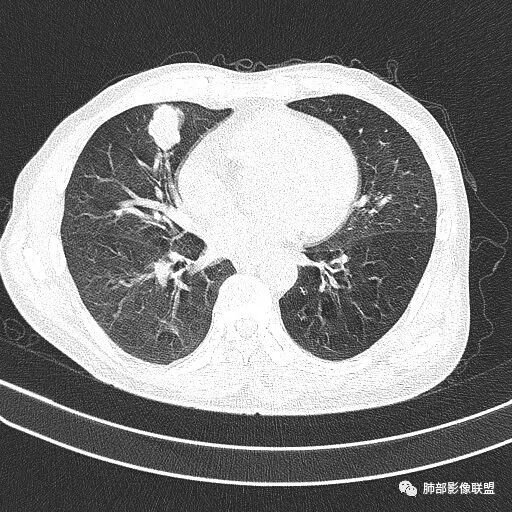

晨读病例  患者老年男性,因腰腹部疼痛3周,排尿困难1周入院。查尿常规及C反应蛋白提示泌尿系感染。肿瘤标志物NSE、细胞角蛋白19片断稍升高。胸部CT:右肺中叶内侧段类圆形肿块影,浅分叶,部分层面见深分叶,胸膜牵拉及支气管截断征象,边界清,密度低,无强化,且垮叶裂。综合考虑恶性病变,类癌及小细胞可能性大,鉴别囊肿等良性病变肺囊肿。

实性还是GGO?      实性

边界清楚、光滑?     光滑清楚,浅分叶,无明显毛刺

与支气管关系如何?   能看清楚吗

如果这时候我建议补充下面的层面,最好薄层

看起来堵了

薇:各位老师,下面是该病例的横断位薄层

1.右肺中叶孤立不规则块影,浅分叶,未见液化或钙化,未见毛刺,未见脐凹,未见明显胸膜牵拉。

2.近肺门侧隐约见支气管截止。

3.外侧可见血管进入,病灶局部轻度强化。